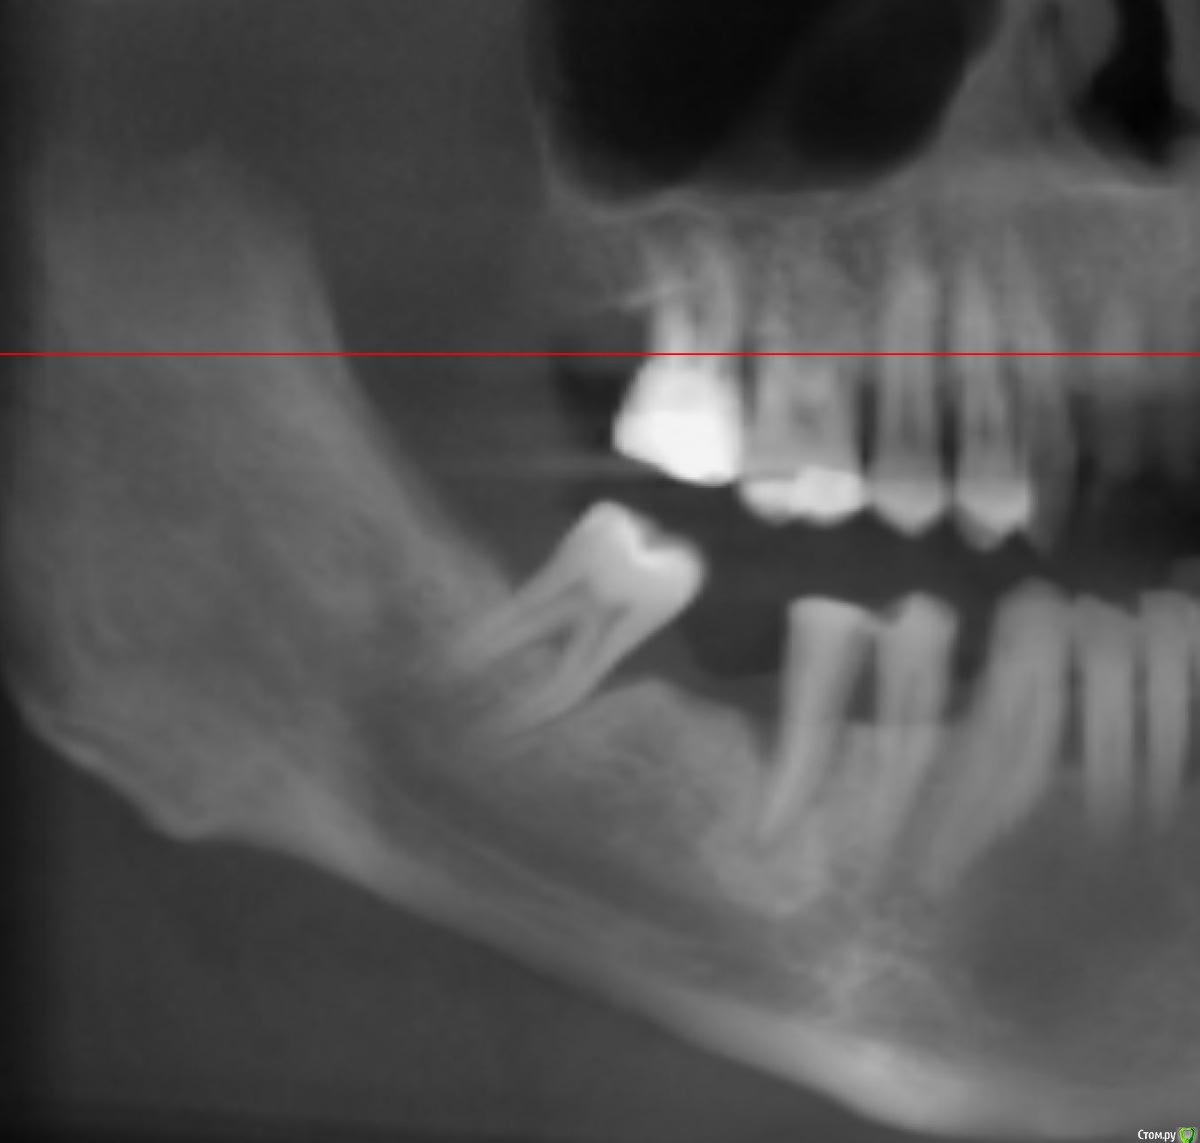

x4ex Опубликовано 8 сентября, 2017 Поделиться Опубликовано 8 сентября, 2017 Добрый день, коллеги! Планируется удаление 45 с последующей имплантацией. Но также нужно медиализировать 44 и дистализировать 47. Чем можно выполнить данное задание? Подойдёт ли EZSpacer? Есть ли другие аппараты для данных целей? Ссылка на комментарий

Ibulat_1986 Опубликовано 18 сентября, 2017 Поделиться Опубликовано 18 сентября, 2017 вокруг 45 кратеообразный дефект - перемещать его лучше ортодонтически, в идеале подключить имплантат через временную коронку Ссылка на комментарий